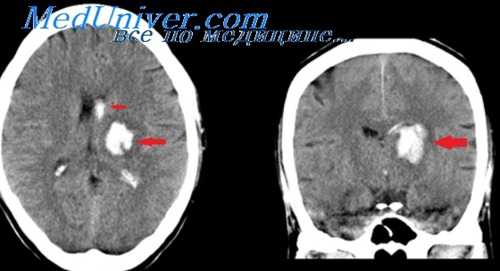

Инфаркт на ранних стадиях, ишемические очаги в стволе, мозжечке и височной доле, не доступные для КТ, венозный тромбоз

В подострой стадии - геморрагические и негеморрагические контузионные очаги, петехиальные кровоизлияния. В хронической стадии обнаруживаются зоны энцефаломаляции на Т2-изображениях по увеличению интенсивности сигнала из-

за повышенного содержания воды в ткани, легче диагностируются внемозговые скопления жидкости, в том числе хронические субдуральные гематомы.